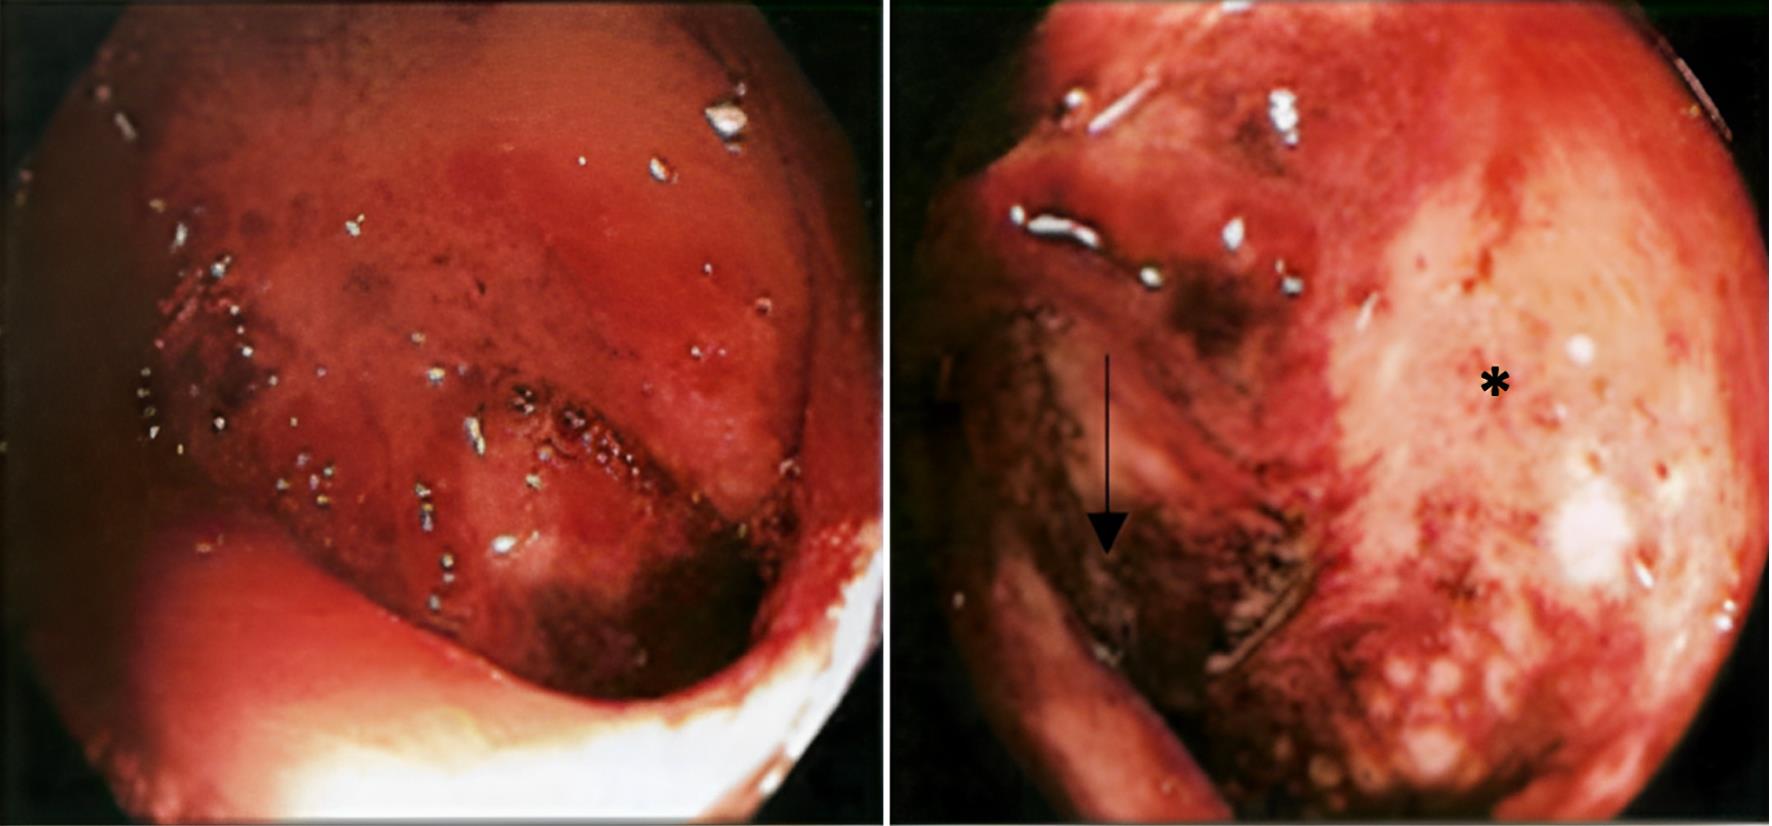

A rectosigmoidoscopy showed ulceration and loss of the normal colonic vascular pattern 30 to 50 cm distal to the anal margin (Fig. 1). Histopathology of the affected area is shown in Figure 2. To rule out conditions beyond the colon, a computed tomography (CT) enterography was performed, which revealed only an inflammatory process in the descending colon (Fig. 3). A colonoscopy confirmed ulceration and inflammation of the colonic mucosa at this site. On the fifth day of hospitalization, the patient experienced another episode of intense abdominal pain and bloody diarrhea one hour after zolmitriptan 2.5 mg was administered for a new migraine episode. After this episode, zolmitriptan was discontinued, and dexamethasone (4 mg intravenous single dose) was initiated. Topiramate was also prescribed, resulting in the complete resolution of the migraine attacks. A neurologic workup for the chronic migraine without aura revealed no organic cause.

A clinical photograph of the colonic mucosa during endoscopy of the descending colon, revealing necrotic areas (black arrow) and abnormal vascular patterns (black asterisk).

Fig. 1  A clinical photograph of the colonic mucosa during endoscopy of the descending colon, revealing necrotic areas (black arrow) and abnormal vascular patterns (black asterisk).